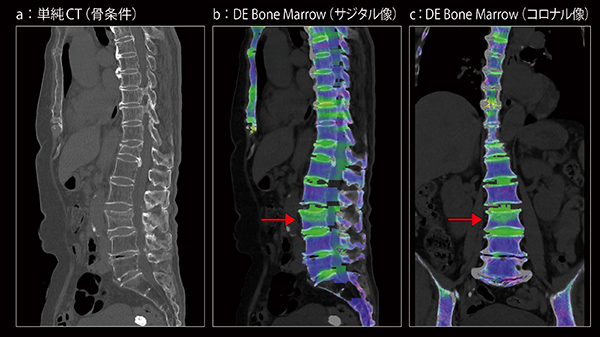

82歳,女性。ベッドから転落し腰背部痛にて救急受診。圧迫骨折疑いにて第5胸椎〜仙骨の広範囲のCT撮影依頼があった。SOMATOM X.citeでは,Dual Energy CTに,“TwinBeam Dual Energy”と“TwinSpiral Dual Energy”の2方式を使用できるが,椎体は呼吸性移動が少ない部分であるので,エネルギー弁別に優れるTwinSpiral Dual Energyで撮影した。骨条件画像では第12胸椎と第3腰椎に変形を認める。DE Bone Marrow画像では第3腰椎(→)に信号値の上昇を認め,第3腰椎の新鮮圧迫骨折と診断された。

医真会八尾総合病院では,ほとんどの領域の検査でmyExam Companionを利用している。SOMATOM X.citeの稼働後も,検査目的に応じてアレンジを加え,前機種の時に作成していたマニュアルも参考にして適用範囲を拡大している。特に,整形外科領域の検査では,すべてにmyExam Companionを使用している。CT更新の大きな目的でもあったDual Energy CTでも,myExam Companionを活用。救急の脊椎骨折,股関節骨折疑いでは全例でDual Energy CTを撮影し,Inline Resultsで自動解析された“DE Bone Marrow”画像を提供している。DE Bone Marrow画像は,整形外科医からも新鮮・陳旧性骨折の鑑別に有用との高い評価を受けている。今後症例を積み重ねていくことで,将来的にはMRIを省略するなど検査のディシジョンツリーが変わる可能性がある。